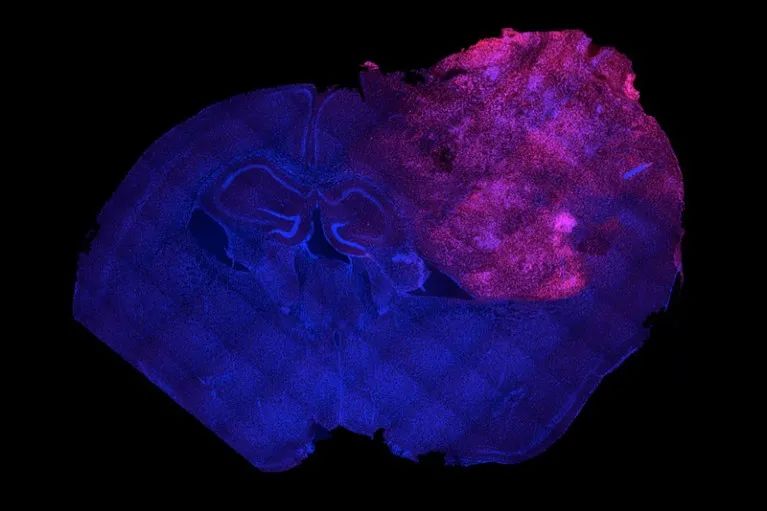

由干细胞制成的人类脑细胞(紫色)在小鼠大脑(蓝色)的部分区域中生长。来源:Raquel Real, Manuel Peter, Rick Livesey and Vincenzo De Paola